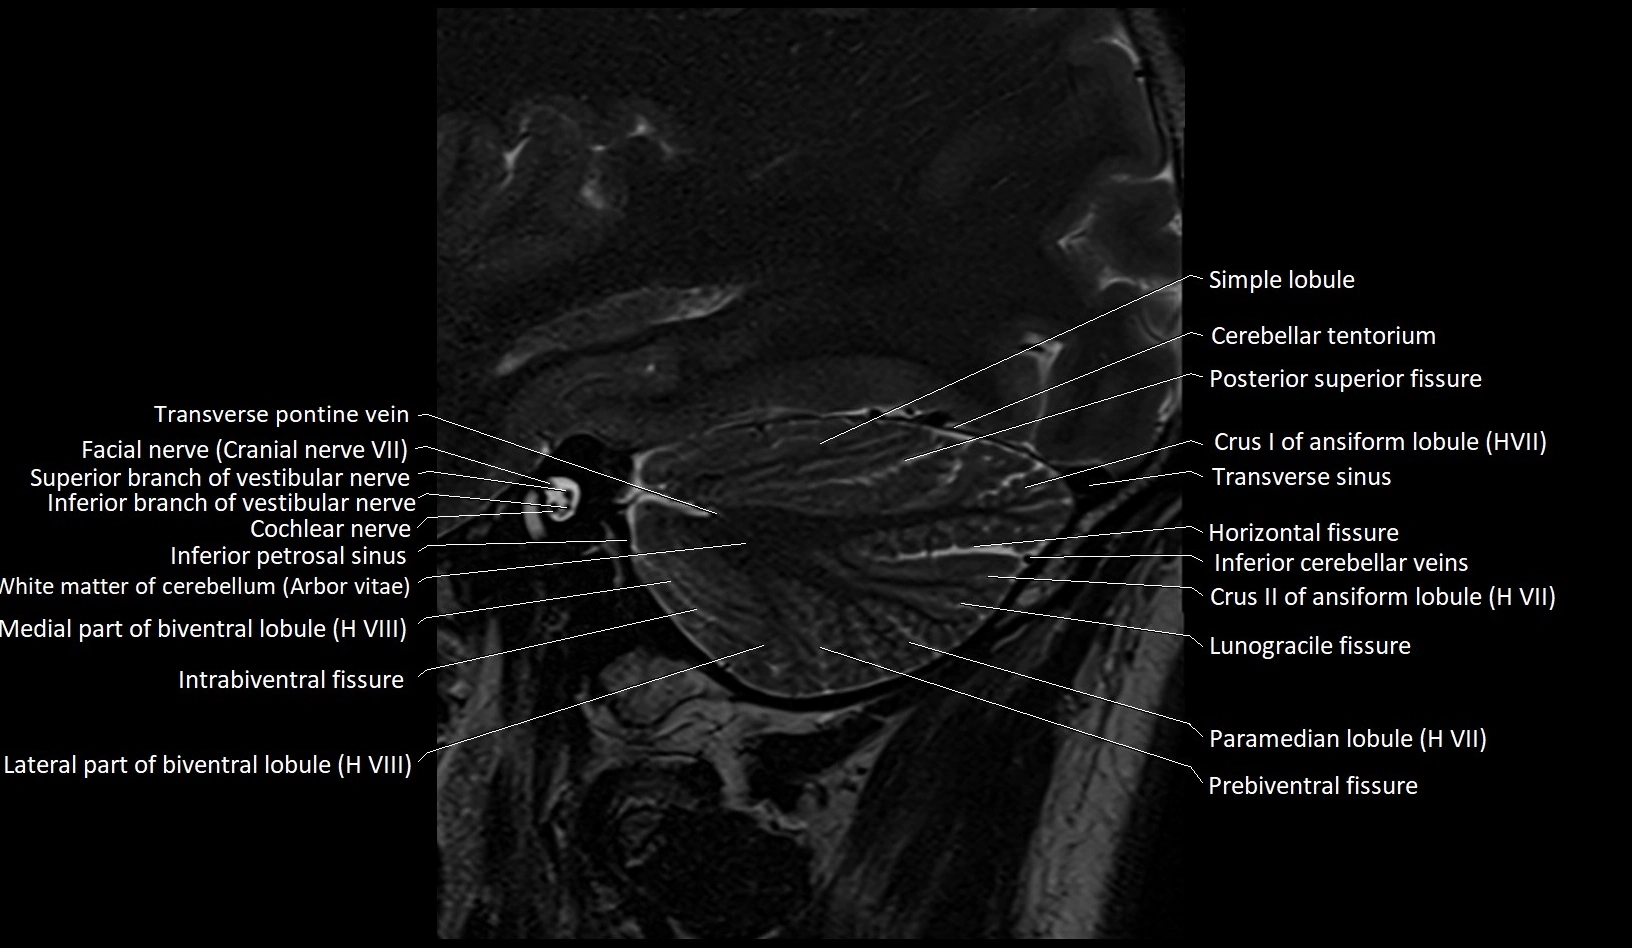

- Biventral lobule (HVIII) of cerebellum

- Cerebellar tentorium

- Crus I of ansiform lobule of cerebellum

- Crus II of ansiform lobule of cerebellum

- Facial Nerve (Cranial nerve VII)

- Horizontal fissure (cerebellum)

- Inferior branch vestibular nerve

- Inferior cerebellar veins

- Inferior petrosal sinus

- Intrabiventral Fissure of Biventral Lobule

- Lateral part of biventeral lobule

- Lunogracle fissure

- Lunogranicile fissure of cerebellum

- Medial part of biventeral lobule

- Paramedian lobule

- Paramedian lobule (HVII) of cerebellum

- Posterior superior fissure

- Prebiventral fissure

- Simple lobule

- Superior branch of vestibular nerve

- Transverse pontine vein

- Transverse sinus